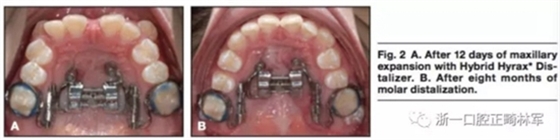

局麻下將兩枚2mm*9mm的微種植體植入鄰近腭中縫處。在上頜第一前磨牙處使用不銹鋼絲。使用聚乙烯硅氧烷上頜取模以制造Hybrid。局麻下翻開粘骨膜瓣使用4枚皮質(zhì)釘以在下頜前牙放置鈦板。通過轉(zhuǎn)動矢狀向的螺釘90°4次以激活擴弓器,0.2mm每次,0.8mm每天。鈦板使用皮筋在兩側(cè)直接加400g前牽力。12天后,上頜前磨牙間橫向?qū)挾仍黾拥?mm。(圖2,A)矢狀螺釘在磨牙遠移階段固定,每周激活雙側(cè)遠移螺釘(0.2mm每周)。8個月后磨牙遠移4mm(圖2B),該階段繼續(xù)掛皮筋。